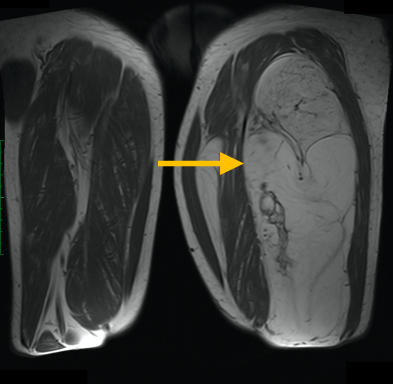

Round Cell Liposarcoma is a malignant, or cancerous, soft-tissue sarcoma that most commonly occurs in the deep tissues of the thigh, or other extremities. It is fairly aggressive and has a greater potential for metastasis.